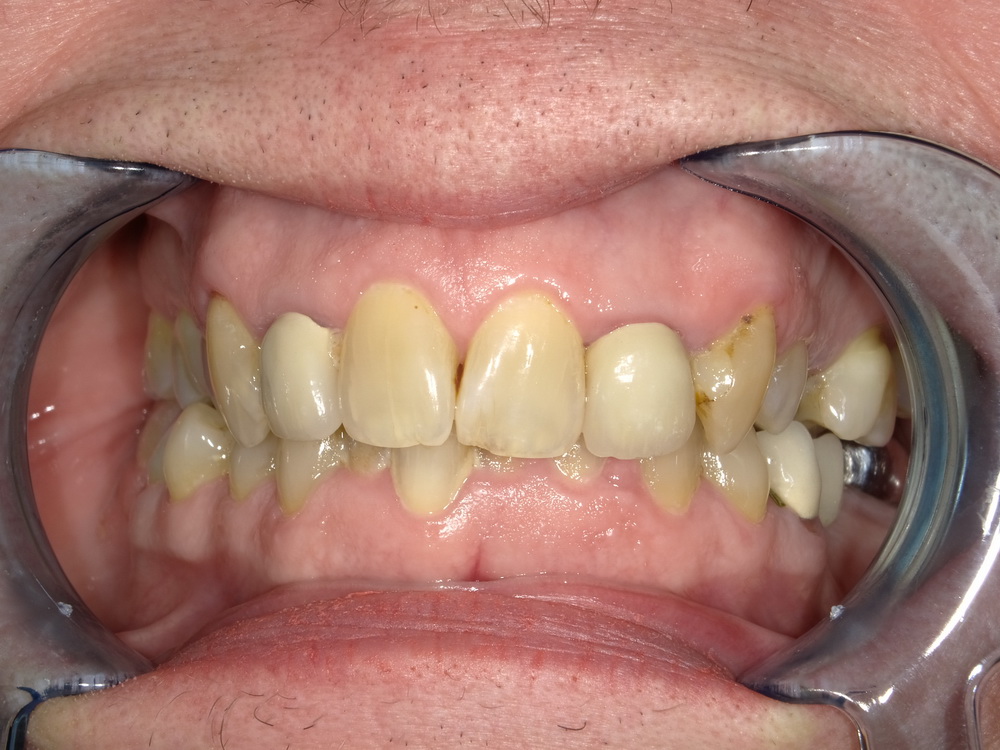

CMD-Patientin ausdem Schaumburger Land beginnt mir der Funktionstherapie

Nun soll es losgehen, was in den vergangenen Monaten systematisch vorbereitet wurde.

Es beginnt mit der Versorgung der Oberkieferseitenzähne mit Laborgefertigten Dauerprovisorien.

Das war der Zustand im September 2025.